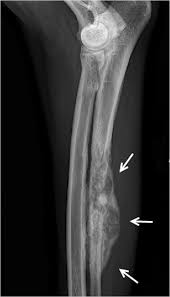

It is caused when the cartilage between joints becomes less smooth and damaged, causing the surface of the bone to rub together and your dog's joints to. Initial symptoms can be subtle and easily missed. Unfortunately, arthritis in dogs is very common. In dogs, bone cancer also can occur as a primary or metastatic disease, but in contrast to humans nuclear scintigraphy is very sensitive, but not specific to identify lesions associated with osteosarcoma, as any region of osteoblastic (bone growth or remodeling) activity will be identified (i.e., arthritis). Diagnosis requires a biopsy to differentiate the condition from other dog skin.

Many pets with arthritis develop a transient or tumors can begin either directly in the affected bone, or cancer cells can spread by a process known as metastasis, from other sites. In dogs, bone cancer also can occur as a primary or metastatic disease, but in contrast to humans nuclear scintigraphy is very sensitive, but not specific to identify lesions associated with osteosarcoma, as any region of osteoblastic (bone growth or remodeling) activity will be identified (i.e., arthritis). Unfortunately, arthritis in dogs is very common. Bone cancer clinical trials & research. In fact, noncancerous bone tumors are much more common than cancerous ones.

Bone Cancer Osteosarcoma In Dogs Canna Pet from g77v3827gg2notadhhw9pew7-wpengine.netdna-ssl.com Bone cancer most commonly affects the long bones in the arms and legs. The cartilage on the end of the bones is surgically removed, and a bone graft is. Arthritis in dogs is common yet very painful. Some varieties occur primarily in children, while others affect mostly adults. Bone cancer clinical trials & research. Hip and elbow dysplasia in dogs is an inherited condition that results from a malformation in bone development. Diet and exercise will be key in the maintenance of a good quality of life. In many cases, owners believe it is just senile arthritis and muscle spasms and nothing more.